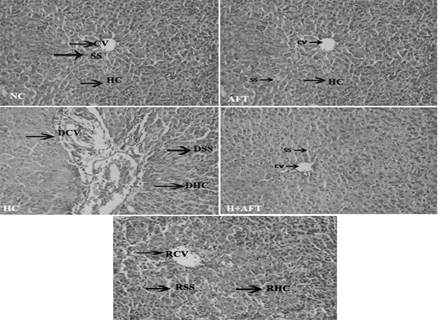

In the Current study, in normal control rats, we observed normal central vein, normal hepatocytes, and normal sinusoids. But in Hepatitis rats, degeneration of central vein (DCV), degeneration hepatocytes (DHC) and degeneration sinusoids (DSS) are seen. However, with PN supplementation in hepatitis rats these hepatic cells like central vein (RCV), hepatocytes (RHC) and sinusoids (RSS) are regenerated.

Fig. 3: Effect of PN on liver tissue during hepatitis condition

In the present study, we observed normal central vein, normal heptocytes and normal sinusoids in the liver of normal control rats. Whereas in Hepatitis rats, we observed degeneration of central vein (DCV), degeneration heptocytes (DHC) and degeneration sinusoids (DSS). However, with PN treatment in hepatitis rats, central vein (RCV), heptocytes (RHC) and sinusoids (RSS) regenerated. This shows the hepatoprotective activity of Phyllanthus Niruri in hepatitis rats. The bioactive and pharmacological compounds of PN in alkaloid fraction may protect the hepatic tissue from hepatitis rats. (fig. 3).